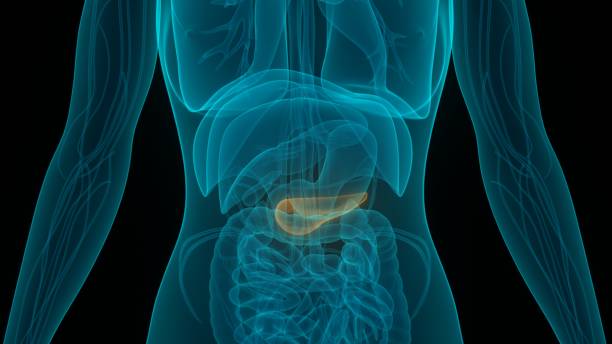

췌장암 초기증상 4. 명치, 등 통증

췌장암 초기증상 네 번째는 명치, 등 통증인데요. 이 부위에서 느껴지는 통증은 췌장이 배꼽과 배꼽 사이의 상복부에 위치하고 있으며 췌장은 위보다 뒤쪽에 더 가깝기 때문인데요. 따라서 요통이 있는지, 배꼽 위쪽에 통증이 있는지 통증의 양태에 따라 자세하게 판단하는 것이 좋아요.